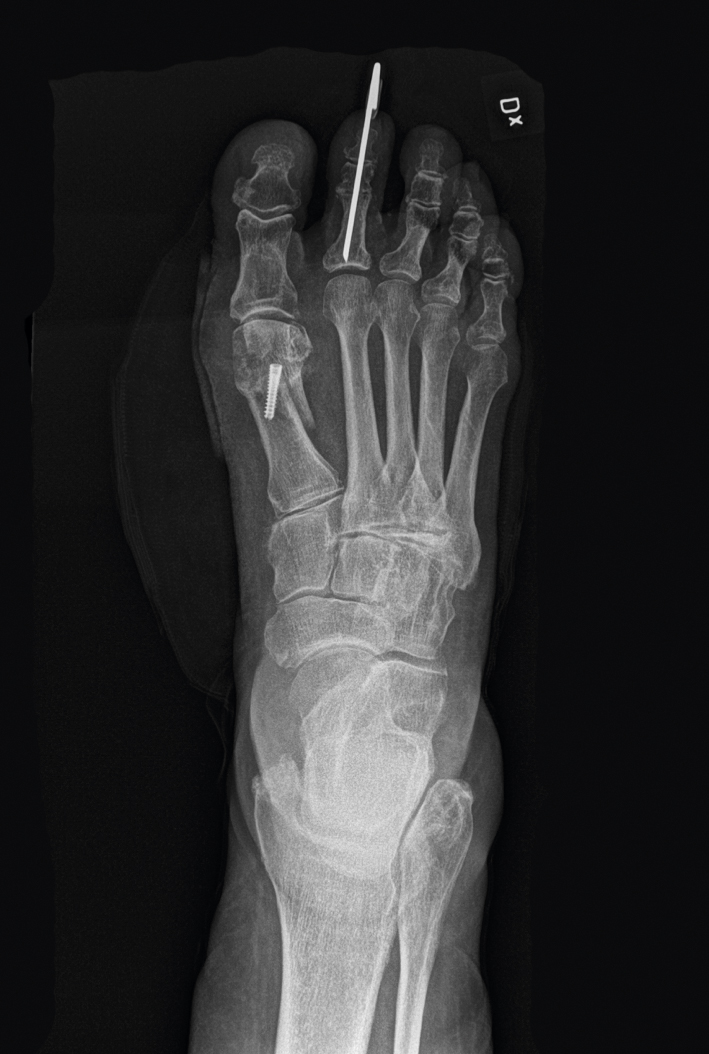

Korrektionsosteotomi subkapitulärt metatarsale I höger, fixerad med skruv, hos en patient med hallux valgus. Notera även stift distalt i andra tån med fixation av de distala och proximala interfalangeallederna på grund av hammartå.